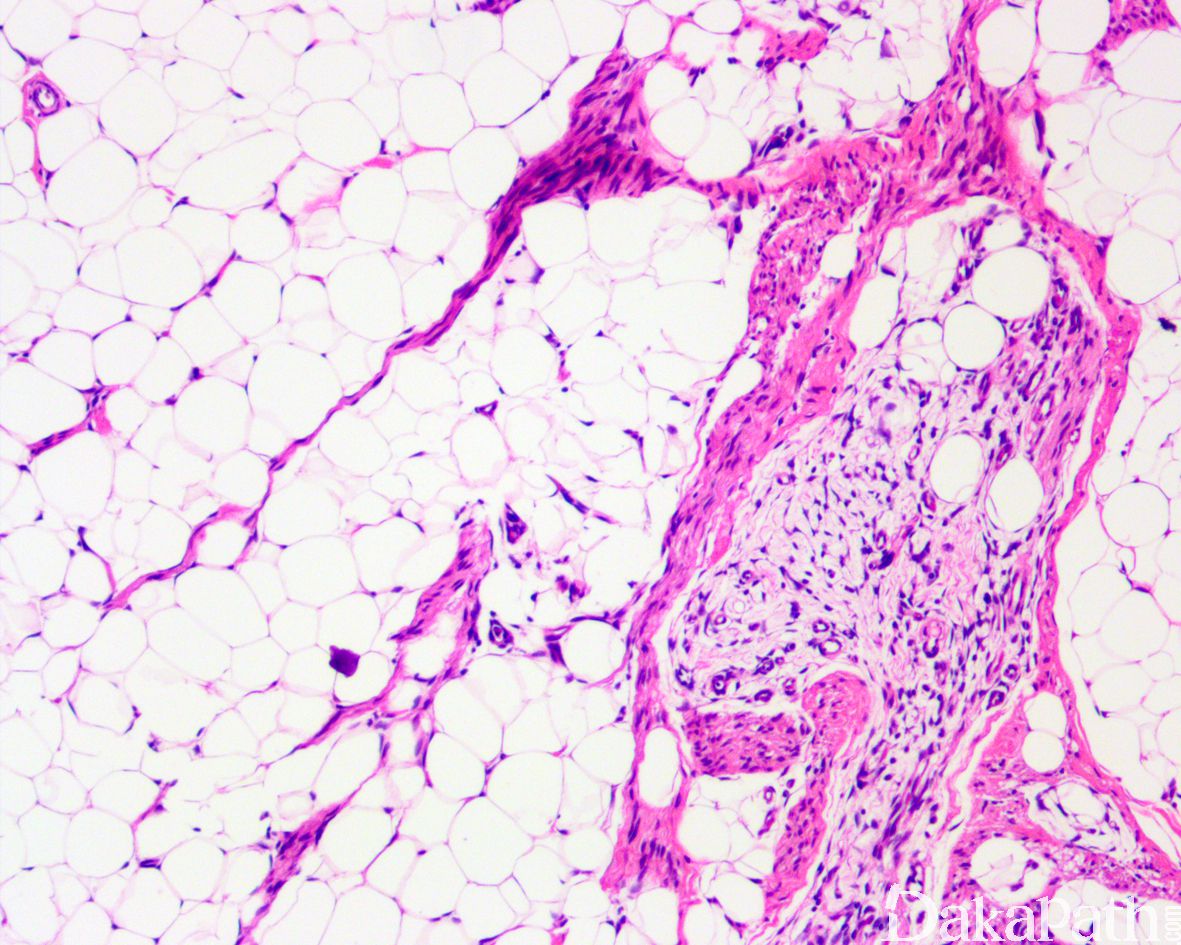

镜下位于真皮深层或皮下,边界不清;由致密梭形细胞、原始间叶细胞和成熟脂肪组织组成,不同病例三者比例不同:

致密的纤维组织由比较成熟的纤维母细胞、肌纤维母细胞和胶原纤维组成,呈纵横交错的束状排列,常呈指状伸入脂肪组织内,组织学类似于纤维瘤病;部分区域可见梭形细胞之间成片的胶原化或瘢痕化以及多核巨细胞沉积,类似于乳腺的假血管瘤样增生或巨细胞纤维母细胞瘤样改变;

原始间叶组织呈结节状分布,由幼稚的短梭形、卵圆形或星状细胞排列成呈疏松的漩涡状、巢状或宽带状包被于富于血管的黏液性基质之间;